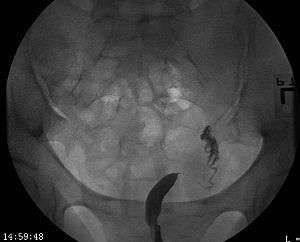

| A unicornuate uterus as seen on a hysterosalpingogram | |

A unicornuate uterus represents a uterine malformation where the uterus is formed from one only of the paired Müllerian ducts while the other Müllerian duct does not develop or only in a rudimentary fashion. The sometimes called hemi-uterus has a single horn linked to the ipsilateral fallopian tube that faces its ovary.